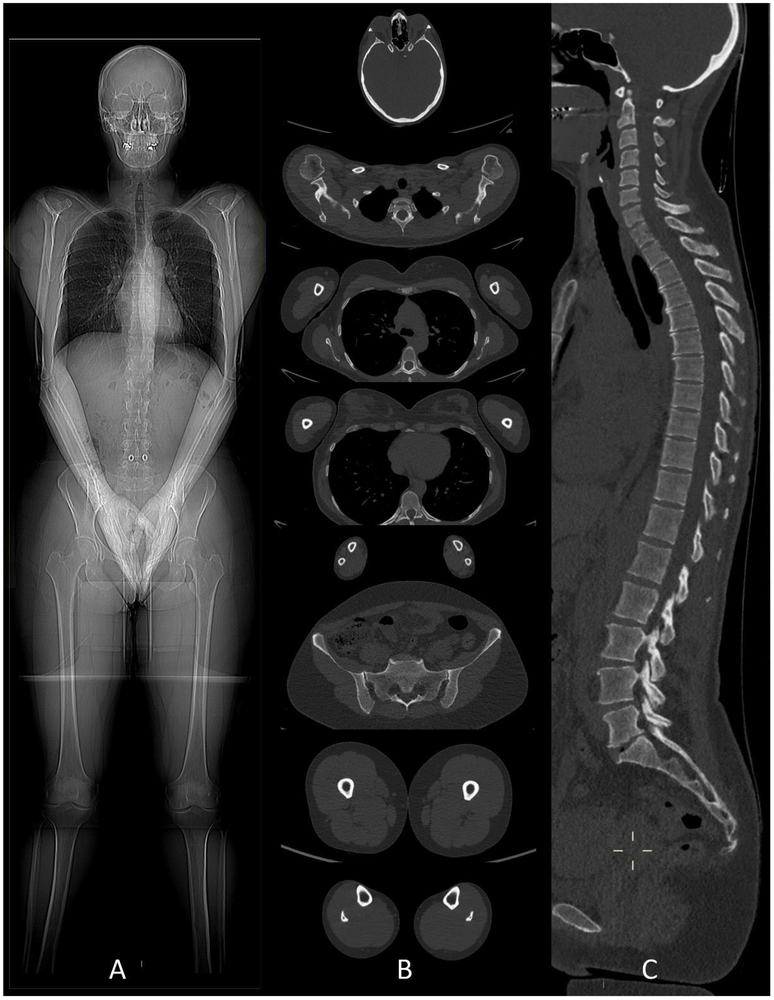

Le scanner corps entier (BODY-SCANNER) introduit en 2001 a révolutionné le bilan du patient polytraumatisé grâce aux évolutions techniques permettant un examen complet dans un laps de temps réduit à quelques minutes avec possibilité d’étude vasculaire. Le body-scanner a participé à la baisse de mortalité et de morbidité des patients polytraumatisés. L’exercice reste difficile pour le radiologue, consistant à interpréter des milliers d’images acquises dans des conditions d’urgences parfois vitales et de gardes souvent peu confortables (nombres d’heures prestées, nuit noire, patients multiples, pression des autres intervenants, stress …).

Figures ci-dessus : Accident de moto sur circuit, intubation sur place. Le body-scanner révèle un hématome sous dural supra-tentoriel gauche, de multiples petites contusions cérébrales hémorragiques, une fracture isolée du condyle occipital droit, une contusion du rein gauche avec lame d’hématome sous capsulaire.